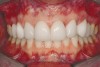

Figure 2d  Prerestorative orthodontics was completed in 5 months. Final result 3 years, 4 months after completion.

Figure 2d

Figure 2e  Teeth Nos. 5 and 12 were converted to Nos. 6 and 11, and Nos. 6 and 11 were converted to Nos. 7 and 10. Nos. 4 and 13 were enlarged. Note stability and absence of orthodontic relapse. Before-and-after smiles.

Figure 2e

Figure 2f  Teeth Nos. 5 and 12 were converted to Nos. 6 and 11, and Nos. 6 and 11 were converted to Nos. 7 and 10. Nos. 4 and 13 were enlarged. Note stability and absence of orthodontic relapse. Before-and-after smiles.

Figure 2f

Figure 2g  Periodontist: Edward P. Allen, DDS, PhD. Prosthodontist: Robert R. Winter, DDS.

Figure 2g

Figure 2h  Periodontist: Edward P. Allen, DDS, PhD. Prosthodontist: Robert R. Winter, DDS.

Figure 2h